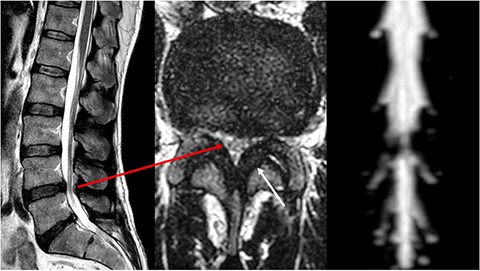

Clinically, the patient was initially diagnosed with a bilateral carpal tunnel syndrome confirmed by electromyogram (EMG)/nerve conduction velocity (NCV) (Fig. 1), which was treated surgically in the typical manner and led to freedom from symptoms. Over the further course, diffuse pain occurred in both legs, and the pain-free walking distance decreased over time. Colour coded duplex sonography (CCDS) did not reveal any evidence of peripheral arterial occlusive disease. Diabetes mellitus could be excluded by laboratory tests. In the imaging diagnostics carried out by means of magnetic resonance imaging (MRI) of the axial skeleton, an absolute spinal canal stenosis at the level of vertebral bodies L4–L5 due to a marked hypertrophy of the ligamenta flava with additional deforming spondylosis could be confirmed (Fig. 2).

MRI of the lumbar spine. Left sagittal slice with a stenosis of vertebral bodies L4/L5, in the axial slice (centre) corresponding stenosis (long arrow) with clear thickening of the ligamenta flava (short arrow). On the right, there is a clear cerebrospinal fluid blockage in the area of the stenosis.